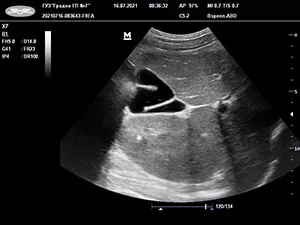

Застой желчи, или билиарный сладж, у детей визуализируется в виде взвеси гиперэхогенных частиц; другие варианты крайне редки. Конкременты выявляются независимо от возраста (даже у пациентов до 3 лет).

УЗИ является одним из основных методов диагностики аномалий развития и приобретенных деформаций желчного пузыря, в то же время в диагностике аномалий протоковой системы данное исследование не всегда информативно.

Рисунок. S-образные формы желчного пузыря. Результаты УЗИ.